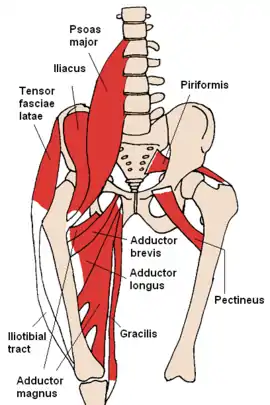

The iliacus and nearby muscles | |

The iliacus is a flat, triangular muscle which fills the iliac fossa. It forms the lateral portion of iliopsoas, providing flexion of the thigh and lower limb at the acetabulofemoral joint.

The iliacus arises from the iliac fossa on the interior side of the hip bone, and also from the region of the anterior inferior iliac spine (AIIS). It joins the psoas major to form the iliopsoas.[1] It proceeds across the iliopubic eminence through the muscular lacuna to its insertion on the lesser trochanter of the femur.[1] Its fibers are often inserted in front of those of the psoas major and extend distally over the lesser trochanter.[2]

The iliopsoas is innervated by the femoral nerve and direct branches from the lumbar plexus.[3]

In open-chain exercises, as part of the iliopsoas, the iliacus is important for lifting (flexing) the femur forward (e.g. front scale). In closed-chain exercises, the iliopsoas bends the trunk forward and can lift the trunk from a lying posture (e.g. sit-ups, back scale) because the psoas major crosses several vertebral joints and the sacroiliac joint. From its origin in the lesser pelvis the iliacus acts exclusively on the hip joint.[2]